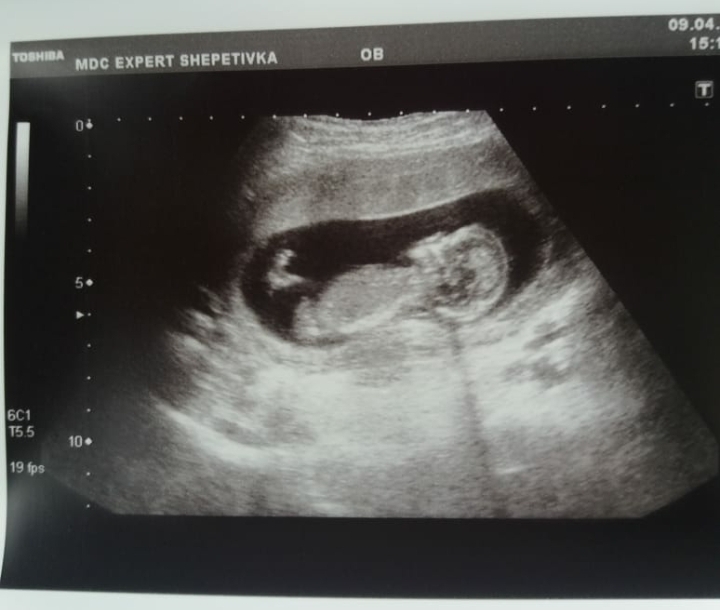

Девчёночки,скажите пожалуйста и мне своё мнение по фото с узи,мальчик или девочки.До следующего узи

Рановато,и девочку можно предположить и мальчика!!!

И на узи сказали рановато.А я всё ищу схожесть с девочкой или мальчиком. Но мой узист очень опытная врач,поэтому если она не увидела,то значит нужно ждать.Как вы считаете на 16-й неделе уже виднее?

вроде краник просматривается:) мужичок скорее всего!

Рентген 17я неделя